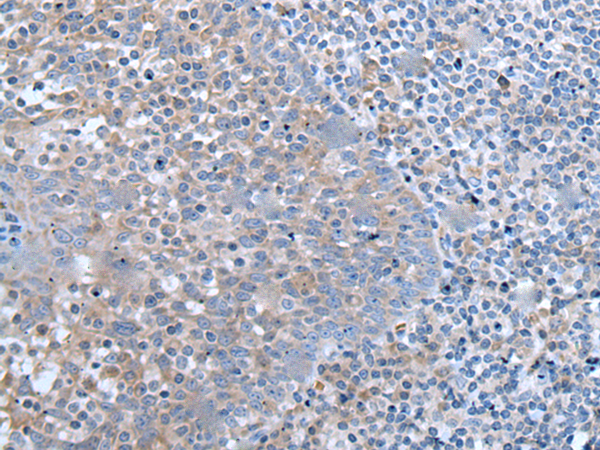

分类: 科研抗体货号: P12833别名:应用: WB,IHC反应种属: Human, Mouse

分类: 科研抗体货号: P12843别名: NLZ1; ZPO1; ZEPPO1; ZNF503L应用: IHC反应种属: Human, Mouse

分类: 科研抗体货号: P12832别名: ZNF913; ZNF-U69274应用: IHC反应种属: Human

分类: 科研抗体货号: P12842别名: HF10; HF.10; Zfp105应用: IHC反应种属: Human

分类: 科研抗体货号: P12862别名: CGI-127应用: IHC反应种属: Human, Mouse

分类: 科研抗体货号: P12841别名: SBF; STAF; pHZ-1应用: IHC反应种属: Human, Mouse, Rat

分类: 科研抗体货号: P12861别名:应用: IHC反应种属: Human, Mouse, Rat

分类: 科研抗体货号: P12840别名: FIM; MYM; RAMP; SCLL; ZNF198应用: IHC反应种属: Human, Mouse

分类: 科研抗体货号: P12860别名:应用: IHC反应种属: Human, Mouse

分类: 科研抗体货号: P12839别名: ZIC; ZNF201应用: IHC反应种属: Human, Mouse